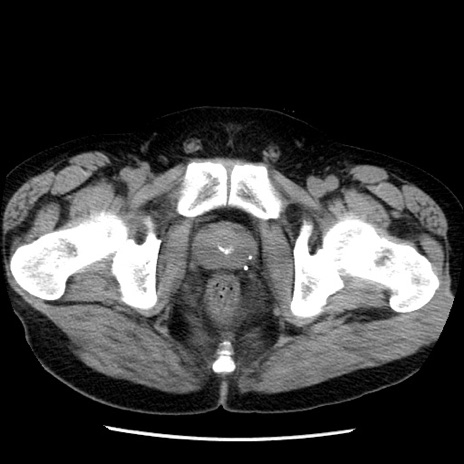

症例29(横断像)

【症例】40歳代男性

【現病歴】2日前から胃痛あり。徐々に周期的な激痛に変化した。本日になっても激痛があるため受診。

【身体所見】意識清明、BT 38-39℃台あり、腹部:膨満、やや硬、右下腹部に圧痛あり。

【データ】WBC 8500、CRP 23.26